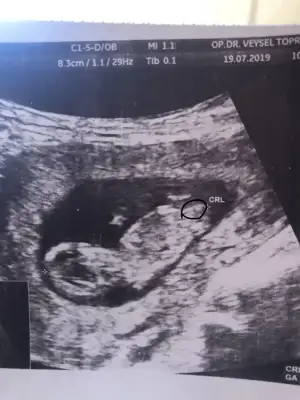

KizzArkadaşlar daire içine aldığım yermi nub oluyor bide yorumlayabilirmisiz lütfen

Tam dik degil ama ben tahminimi Erkek gibi yorumluyorum